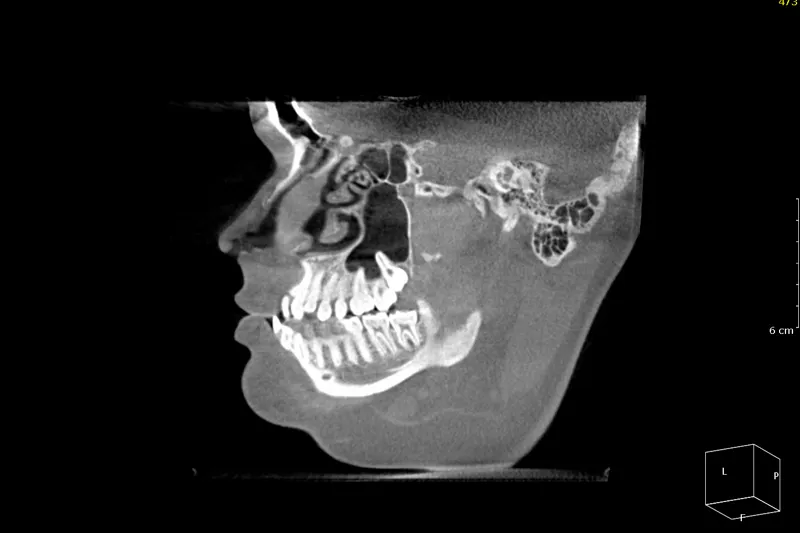

De fleste patienter, der får udført ortodontisk kirurgi, får fjernet deres visdomstænder inden den egentlige behandling. De CBCT-undersøgelser, der optages i forbindelse med ortodontisk kirurgi, har imidlertid et større billedfelt (FOV) og dermed en lavere billedopløsning end de optagelser, der normalt tages før fjernelse af visdomstænder. Forskere fra Aarhus Universitet (Institut for Odontologi og Oral Sundhed) og Sydvestjysk Sygehus, Esbjerg (Kæbekirurgisk Afdeling), har derfor undersøgt, hvor godt forskellige fund på CBCT med stort billedfelt korrelerer med de kliniske fund, der kan registreres i forbindelse med operationen.

209 tredjemolarer fra underkæben blev i perioden 2015- 2017 fjernet på 134 patienter, der var skrevet op til ortodontisk kirurgi. Tre uafhængige eksperter registrerede på CBCT med stort billedfelt tændernes lejring, rodantal og rodmorfologi samt en række parametre, som vedrørte tændernes relation til canalis mandibulae. I forbindelse med operationerne blev de samme tandrelaterede forhold registreret, og i relation til canalis mandibulae blev det registreret, om nerven var synlig efter fjernelse af tanden, om der var furer i roden efter nerven, og/eller om patienten ved suturfjernelsen havde føleforstyrrelser svarende til n. alveolaris inferior.